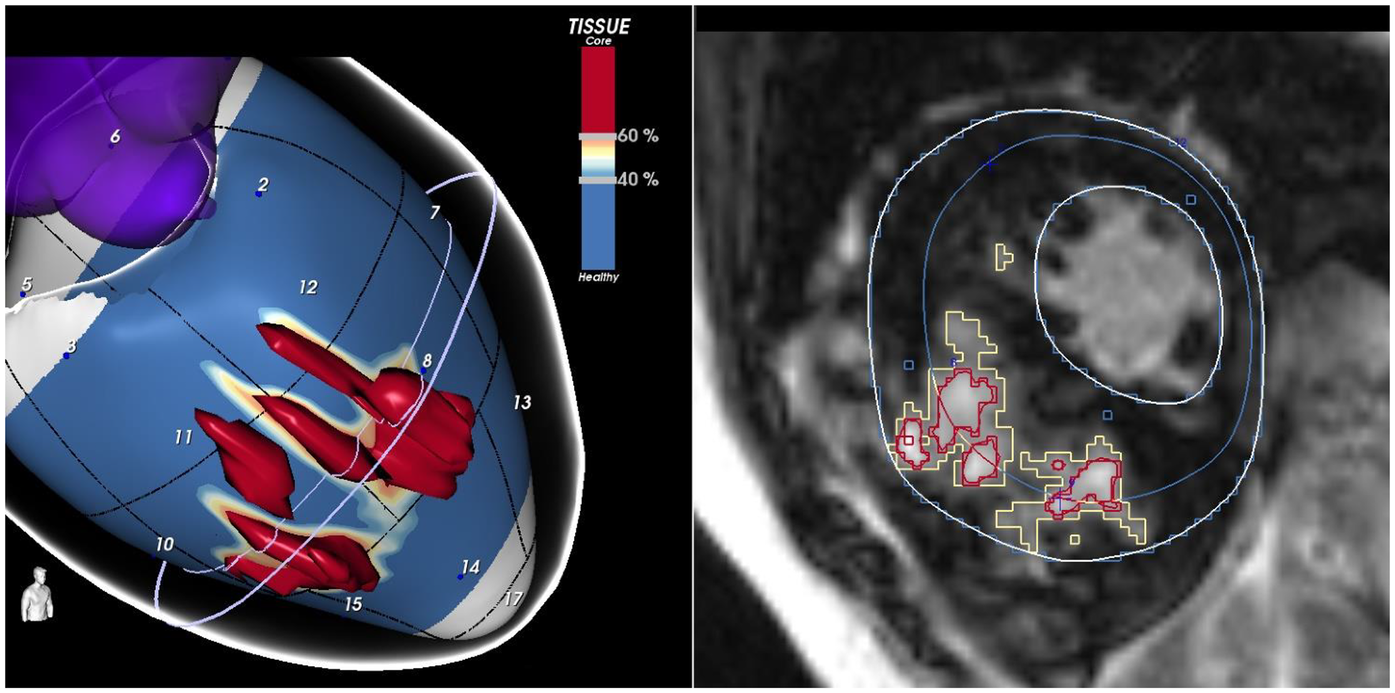

These findings support the notion that a qualitative evaluation of scar architecture, particularly LGE signal heterogeneity, may offer deeper insights into arrhythmic risk. However, conventional 2D LGE imaging has limitations in capturing the full complexity of the three-dimensional scar structure (48). To address this, advanced post-processing software have been developed to improve scar characterization (56, 57). These tools segment signal intensity at the pixel level to differentiate dense core fibrosis from diffuse border zone (BZ) fibrosis and reconstruct the data into 3D images (Figure 1). They identify corridors of BZ tissue surrounded by dense scars or anatomical barriers, which connect regions of viable myocardium, referred to as border zone channels (BZCs) (56). Functionally, BZCs represent slow-conducting pathways composed of excitable myocardium insulated by non-conductive fibrotic tissue serving as substrates for re-entrant VTs (56, 58). Recent CMR data demonstrated that the presence of BZCs is a strong independent predictor of ICD interventions for VT/VF in high-risk HCM patients (59).

Figure 1

The figure shows a short-axis view of a CMR of a patient with HCM, highlighting an extensive scar involving the interventricular septum. LGE-CMR images were post-processed using ADAS 3D (Galgo Medical, Barcelona, Spain), creating nine concentric surface layers spanning from the endocardium to the epicardium of the left ventricular wall thickness, resulting in a 3D shell for each layer. Color-coded pixel signal intensity (PSI) maps were projected onto each shell. Hyper-enhanced areas were classified as the core zone, borderline zone (BZ), or healthy tissue using thresholds of 40 ± 5% and 60 ± 5% of the maximum PSI. The scar-dense core is coded in red, BZ is coded in orange and white, and healthy myocardium is coded in blue.